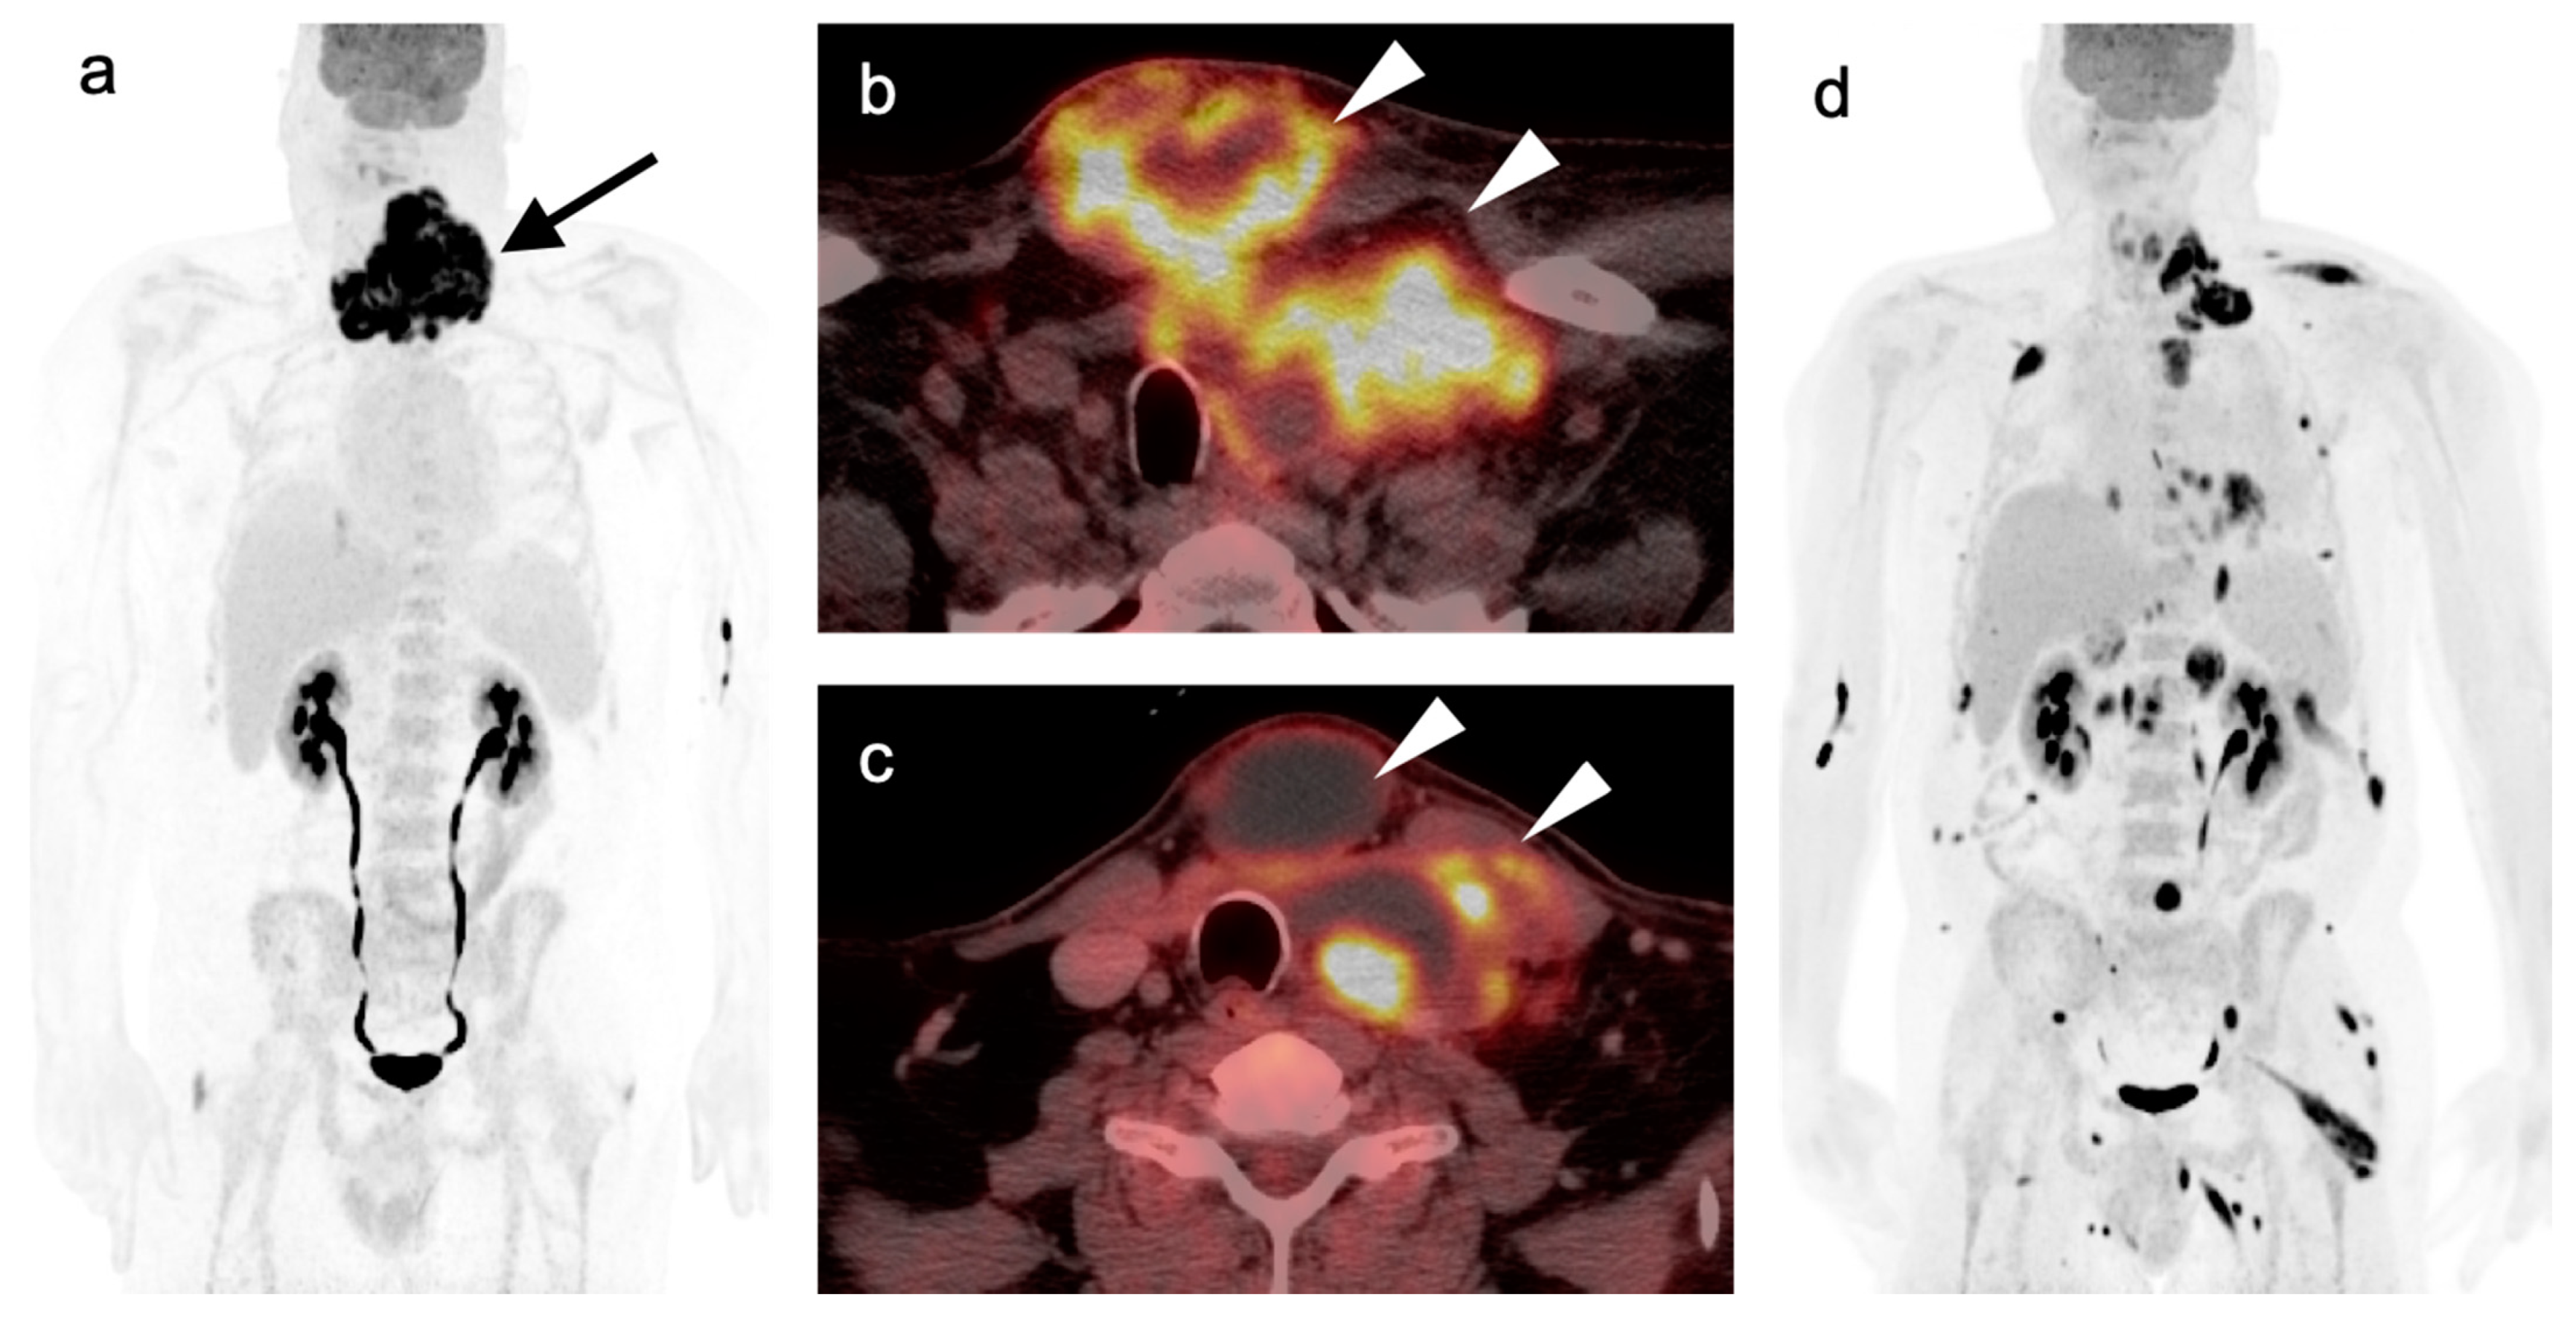

2.2. Squamous Cell Carcinoma of the Head and Neck (SCCHN)

2.3. Nasopharyngeal Carcinoma